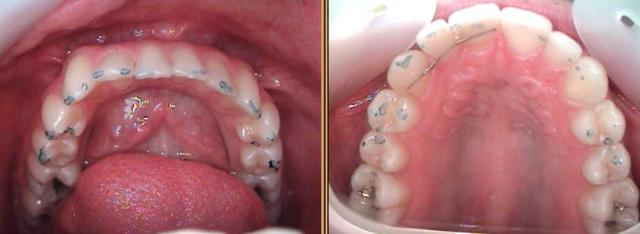

Donc monique a 20 ans; se présente en consult pour des douleurs à la mâchoire, déviation, craquement suite dépose appareil ODF. Puis apparition de migraine ( 1 a 2 fois par mois ) plus des douleurs plus au moins continuelles au niveau des angles goniaques, au niveau temporal.

il y a douleur ++ au PTE ( si 100 % droit, 80 % gauche ), DSD, déviation des milieux, déviation à l'ouverture, ouverture maximal instable, AFMP inégaux avec une fonction gauche, mississipi semble trop petit ? avec un léger chuintement.

- Constat : « Contention définitive » supérieure / inférieure = je hais = impossibilité de permettre l’hygiène interdentaire = ineptie ODF « moderne » convoitée arbitrairement par la Hautre Autorité de la Santé, Anaes (France) (1) sans accorder la moindre importance (Bravo ! ) à la DSI = récidive assurée dès que l’attelle « tombera », puisque DSD confirmée par palais étroit et haut + empreintes dentaires sur les faces latérales de la langue + etc. !